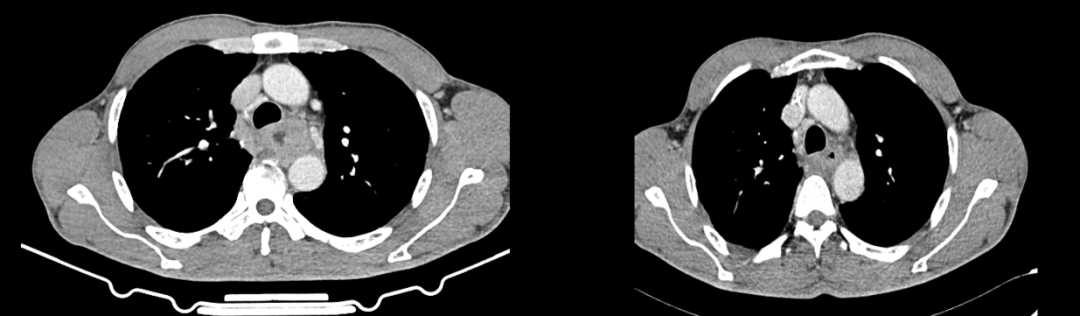

胸部CT:食管中上段部分管壁不规则增厚,考虑食管癌;邻近周围多发肿大淋巴结,与气管、左主支气管及主动脉分界不清。

复查CT:食管中上段部分管壁不规则增厚,较前缩小,邻近周围多发小至稍大淋巴结,较前缩小。邻近气管及左主支气管受压已基本缓解,病灶向后与主动脉前壁分界不清。